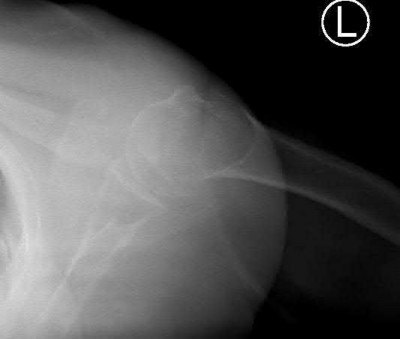

Question 12:

A 55-year-old patient presents with a slowly enlarging, painful mass in the proximal humerus. Biopsy reveals a hyaline cartilage matrix with cellular atypia, confirming a diagnosis of central conventional chondrosarcoma. Which of the following genetic mutations is most frequently identified in this specific tumor?

Correct Answer: IDH1 / IDH2

Explanation:

Mutations in the isocitrate dehydrogenase genes, IDH1 and IDH2, are found in up to 50-60% of central conventional chondrosarcomas and enchondromas. EXT1 and EXT2 mutations are characteristic of multiple hereditary exostoses (osteochondromas). GNAS mutations are seen in fibrous dysplasia. TP53 and RB1 mutations are hallmark aberrations in osteosarcoma.